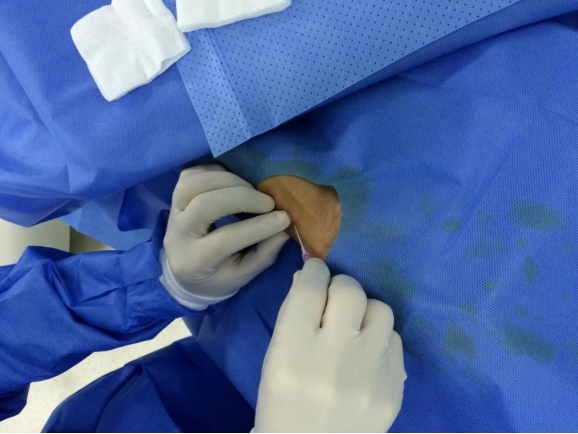

穿刺:

操作者右手持注射器,左手食指和中指轻触受试者右桡侧探明桡动脉路线,于右桡侧第二掌横纹下1.5cm左右搏动较强处垂直刺破皮肤,再调整针尖角度为30-40°沿左手食指搏动最强处前向刺入,直至穿刺针尾部冒血。

穿刺要点

两点法:两个桡A搏动点以明确血管走行;穿刺点:桡骨茎突近心端水平;角度:30度左右;穿刺法:穿透法比喷血法好;少用局麻:皮下,少于0.5ml利多;预防痉挛:硝酸甘油200μg鞘内注射;穿透法喷血后左手扶针鞘,缓慢退鞘,手一定要稳;导丝进入困难时建议导丝塑弯透视下调整。